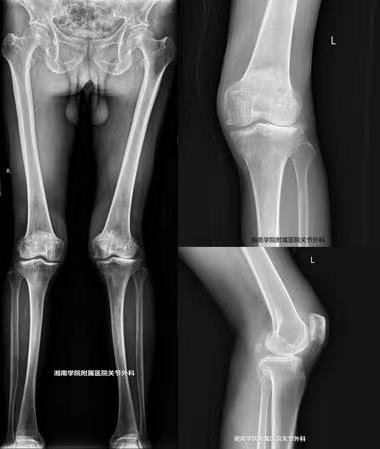

由于谢爷爷不会说普通话,只会讲嘉禾方言,给医患沟通带来一定难度。经过主管医生谷四全的耐心沟通、详细问诊及完善检查,发现谢爷爷左膝呈外翻畸形(俗话说外八字),膝疼痛集中在外侧,X片和核磁共振提示谢爷爷左膝还存在外侧间室骨质增生、软骨剥脱、外侧半月板脱位等情况,不适合做修复性治疗。

骨一科主任唐新文根据谢爷爷病例特点组织查房讨论,考虑患者病程不长,其他关节间室退变不重,韧带完整,应力下膝关节外翻可部分矫正,膝关节活动度稍受限,结合患者后续生活质量需求,认为相较于全膝关节置换术,单髁置换术更适合。